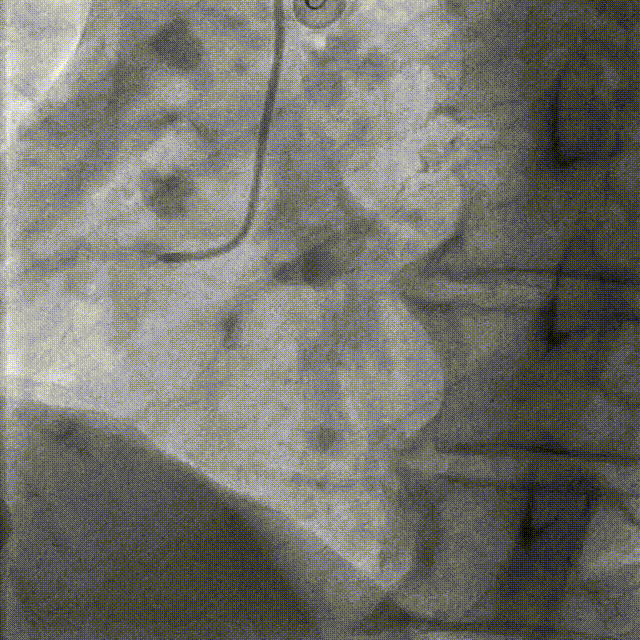

CAG-LCA-钙化、 分叉 、弥漫病变 TR, 5F TIG

CAG-RCA -钙化,开口,弥漫病变 TR, 5F TIG

RCA:钙化,开口,弥漫病变

LAD:钙化,分叉,弥漫病变

LCX:细小,可不处理

PCI-RCA TR, 7F JR4.0 ROTA with 2.0mm burr

Angiography post-ROTA